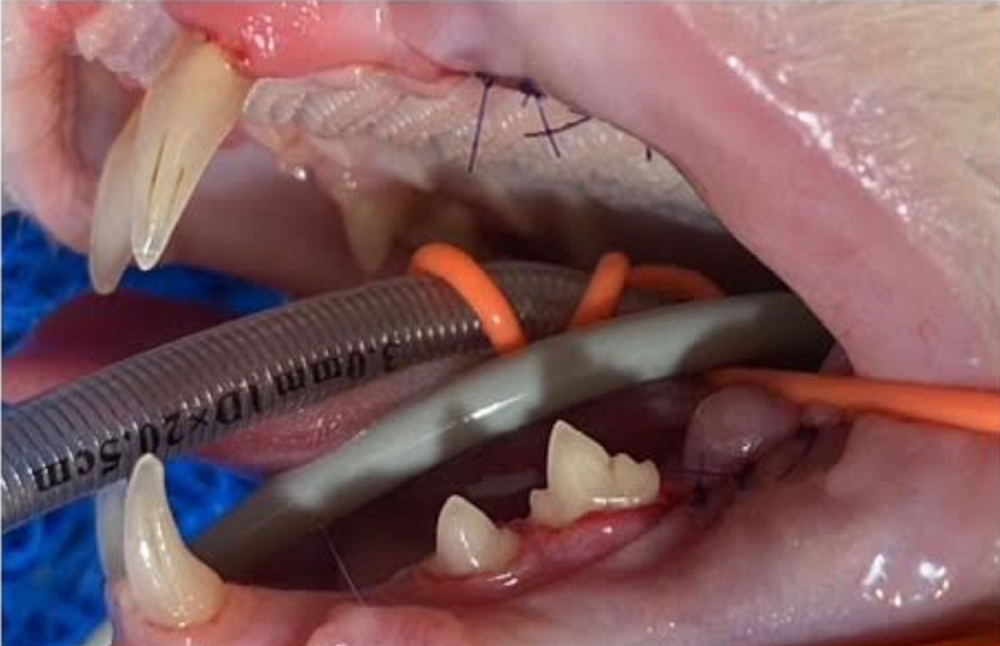

Die grösste Baustelle aber war und ist ihr Gebiss:

Bisher wurde eine Seite behandelt, einige Zähne sind dabei praktisch fast von alleine raus gefallen andere mussten gezogen werden.

Da ihr aufgrund ihres Alters keine zu lange Narkose zugemutet werden sollte, wurde erst eine Seite ihres Gebisses gemacht, die andere Seite folgt in einigen Wochen.

Bereits jetzt speichelt sie weniger und macht allgemein einen besseren Eindruck. Karisma hat vermutlich viele Jahre unter schlimmen Zahnschmerzen gelitten.